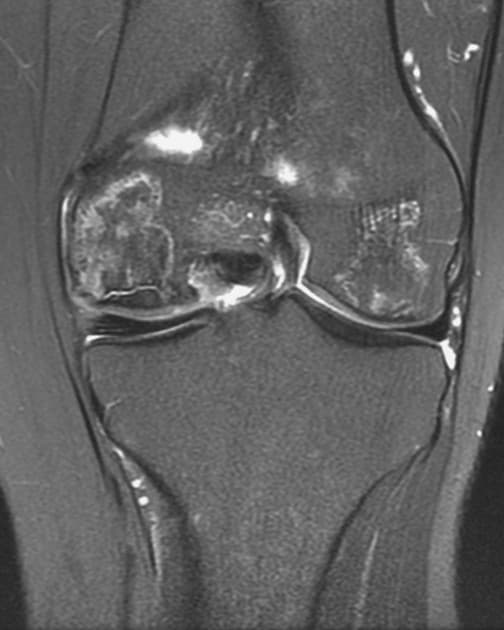

- Gãy lồi cầu ngoài xương chày lệch vị trí kèm theo tràn dịch mỡ-xuất huyết khớp gối (lipohemarthrosis) lớn.

- Gãy vụn (comminuted fracture) lồi cầu ngoài xương chày, tổn thương có vẻ lan tới các gai gian lồi cầu (intercondylar spines).

- Các mảnh gãy chính của lồi cầu ngoài xương chày bị tụt xuống ít nhất 5 mm, khe gãy rộng hơn ở phía trước so với phía sau.

- Gãy kèm theo vùng nối đầu-cổ xương mác (fibular head/neck junction).

Gãy vụn kết hợp gãy tách và gãy nén lồi cầu ngoài xương chày, kèm theo gãy vùng đầu/cổ xương mác và tràn dịch mỡ-xuất huyết khớp gối (lipohemarthrosis) lớn.

Gãy lồi cầu ngoài xương chày là tổn thương nội khớp, thường xảy ra do kết hợp lực biến dạng kiểu varus và tải trọng dọc, dẫn đến nén và tách lồi cầu ngoài. Sự hiện diện của tràn dịch mỡ-xuất huyết khớp là dấu hiệu hình ảnh học quan trọng, cho thấy xuất huyết và mỡ trong khớp, thường liên quan đến gãy kín. Trong trường hợp này, gãy vụn, mặt khớp bị tụt xuống hơn 5 mm, lan tới các gai gian lồi cầu, kèm theo gãy vùng đầu/cổ xương mác. Những phát hiện này gợi ý chấn thương năng lượng cao và làm tăng nguy cơ tổn thương sụn chêm hoặc dây chằng. Điều trị phẫu thuật, như nắn chỉnh mở và cố định nội (ORIF), thường được chỉ định để phục hồi độ khít khớp và ngăn ngừa thoái hóa khớp sau chấn thương. Chẩn đoán hình ảnh chính xác, bao gồm CT hoặc MRI, là cần thiết để lập kế hoạch phẫu thuật.